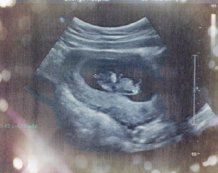

看,28周的你,已经是个小小人了,最有特点的就是你圆圆的小脑袋。

这是你在妈妈肚子里14周-36周的变化,妈妈悄悄把它记录下来了。